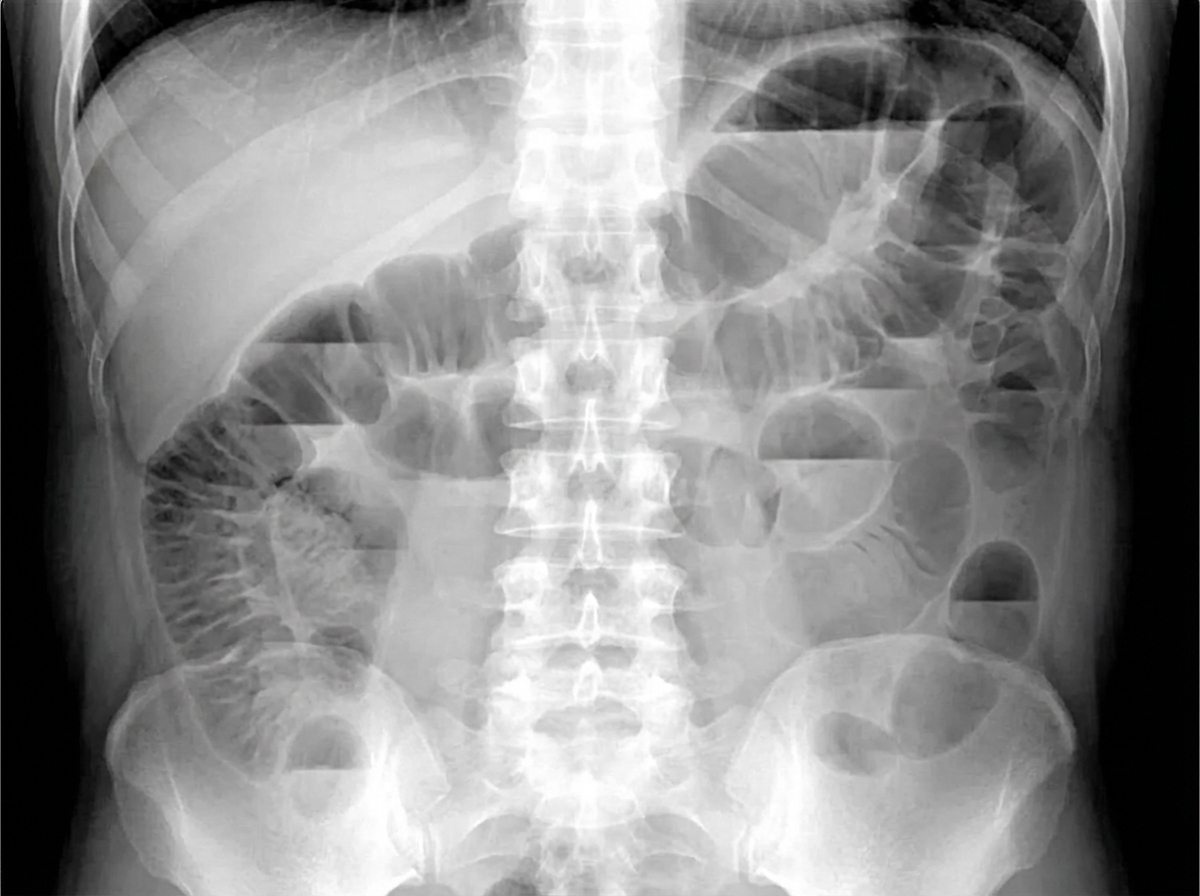

A 14-year-old boy is brought to the emergency department because of abdominal swelling and vomiting over the past 24 hours. He has generalized abdominal pain. He has no history of any serious illnesses and takes no medications. His temperature is 36.7°C (98.1°F), blood pressure is 115/70 mm/Hg, pulse is 88/min, and respirations are 16/min. Abdominal examination shows diffuse swelling with active bowel sounds. Mild generalized tenderness without guarding or rebound is noted. His leukocyte count is 8,000/mm3. An X-ray of the abdomen is shown. Intravenous fluids have been initiated. Which of the following is the most appropriate next step in management?